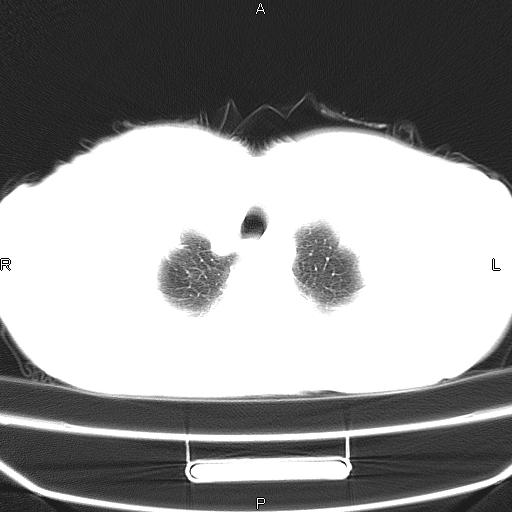

患者,女,66岁。健康体检胸部透视发现右上肺片状阴影。既往无不适,患者自诉三个月前曾有低热病史体温37.5左右一周。用药后缓解。至今无其它不适。请老师们指导指导。

考虑:右肺上叶周围型肺癌(分叶状肿块+砂粒状钙化+胸膜尾征)。

病灶见明显分叶、大小较大(大于3cm?),老年人,多考虑:肺癌,建议穿刺活检。

典型的中心型肺癌,尖段支气管阻塞。

右肺上叶周围型肺癌可能性大。

考虑:右肺上叶周围型肺癌